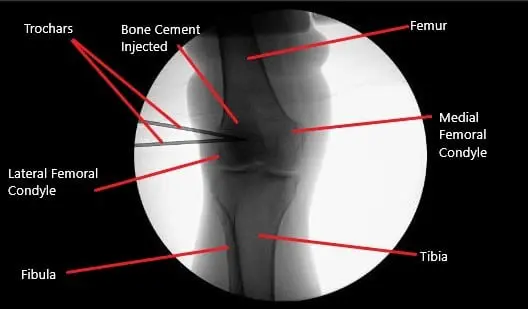

Intraoperative fluoroscopic image of the right knee showing tricalcium phosphate bone injection.

Now the focus was directed to the excision of the lateral femoral condyle. A fluoroscope was brought into the picture. Under guidance with fluoroscopy, a drill hole was made about 2.5 cm proximal and anterior to the inferior and posterior articular surface of the femoral condyle. It was inserted about 15 mm.

Another drill hole was made with a similar cannula about 0.5 cm proximal and anterior from the previous cannula directed posteriorly and inferiorly in the lateral femoral condyle. Pictures were taken in the AP and lateral view and found to be satisfactory.

Tricalcium phosphate bone cement was mixed and injected about 2.5 milliliters into each cannula and trochar was introduced. Pictures were taken in the C-arm and found cement to be into the bone only. An arthroscope was entered to examine the femoral condyle as well as the intercondylar notch and no bone cement could be seen extravasating there.

The knee scope was removed and the knee was drained completely. The cement was left to set. Once the bone cement was set for more than 12 minutes, the cannula was removed. The final picture was taken with the fluoroscope and saved. The knee was thoroughly drained and the wound was washed.